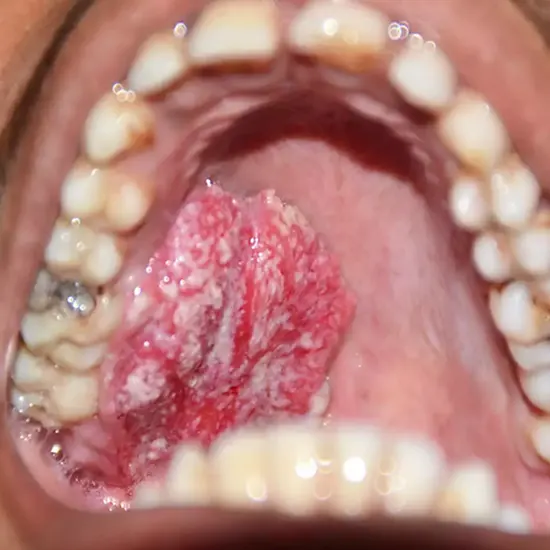

What are the symptoms of Cheek Cancer?

Symptoms of cheek cancer, also known as buccal mucosa cancer or oral cancer, can include:

- A sore in the mouth

- An unhealed lump in the mouth

- Pain in the mouth

How is Cheek Cancer Diagnosed?

Cheek cancer is typically diagnosed through a combination of physical examination, medical history, imaging tests, and biopsy.

Physical examination: Your doctor will first examine your cheeks and mouth for any signs of abnormal growth or sores.

Biopsy: A tissue biopsy is the most reliable way to confirm a diagnosis of cheek cancer. During a biopsy, a small sample of tissue is taken from the affected area and examined under a microscope for signs of cancer cells.